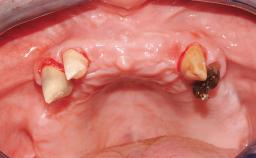

Conventional Loading of Eight Implants in the Maxilla and Final Restoration with a Full-Arch Gold-Ceramic FDP

A 35-year-old Caucasian female presenting with advanced periodontal disease involving both the maxillary and the mandibular dentition was referred for evaluation. The patient, a non-smoker in good general health, requested treatment for recurrent periodontal abscesses, tooth mobility, and discomfort during chewing, as well as restoration of her missing teeth with a fixed prosthesis to improve mastication and esthetics. All residual maxillary teeth exhibited plaque deposits, deep pockets, bleeding on probing, and class III mobility and were evaluated as hopeless. All residual mandibular teeth except tooth 37 could be maintained after periodontal therapy.

| Bone Volume | Deficient vertically or deficient vertically AND horizontally |

| Soft Tissue Contour and Volume | Significantly deficient |